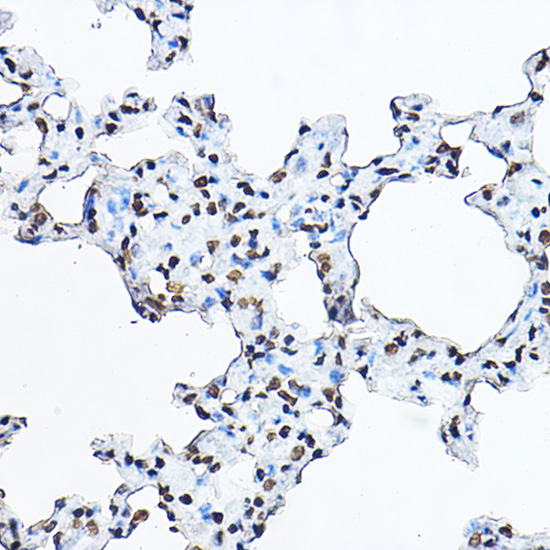

Immunohistochemistry of paraffin-embedded rat lung using Histone H3 Rabbit pAb.